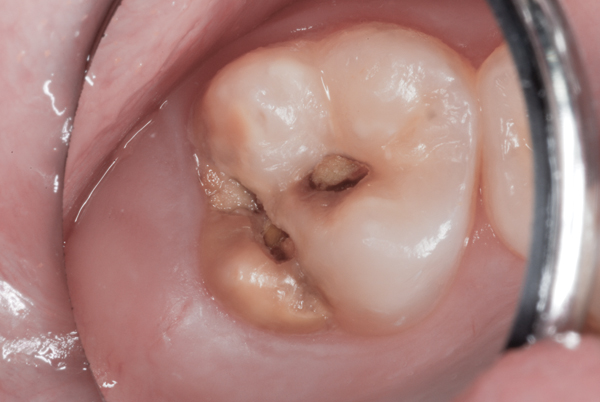

It can affect only a single tooth or multiple teeth. Enamel hypoplasia encompasses all deviations from normal enamel in its various degrees of absence. Enamel hypoplasia in permanent teeth induced by periodontal ligament anesthesia of primary teeth. Enamel hypoplasia is a defect in the enamel due to disturbance of ameloblastic function during amelogenesis. But before we proceed further, what is the enamel? View enamel hypoplasia research papers on academia.edu for free. The etiology of such a disturbance may be either genetic or environmental in nature. Enamel hypoplasia is a term that denotes incomplete or underdeveloped tooth enamel. Enamel hypoplasia is a defect that affects the way the teeth develop, causing them to have poor enamel matrix formation. Do this 60 seconds dental trick before going to bed tonight to rebuild your teethand gums and get rid of tooth decay click to know more. Symptoms of enamel hypoplasia include Useful background review for this subject can be found at: Here we present two cases of linear enamel hypoplasia.

This condition is known as enamel hypoplasia. Research of dental enamel hypoplasia has been linked to hypoplasia, dental caries, tooth abnormalities, amelogenesis imperfecta explore more on dental enamel hypoplasia below! Do this 60 seconds dental trick before going to bed tonight to rebuild your teethand gums and get rid of tooth decay click to know more. Dental enamel hypoplasia, a defect of enamel formation, has been widely used for the investigation of growth disruptions in past. Symptoms of enamel hypoplasia include You could be noticing enamel hypoplasia. Enamel hypoplasia is common in children with low birthweight or systemic illness in the neonatal •enamel hypoplasia (or 4.2) •presence of s. Enamel hypoplasia encompasses all deviations from normal enamel in its various degrees of absence. The etiology of such a disturbance may be either genetic or environmental in nature. That's because they're both defects, often caused by genetic predispositions, that affect the. View enamel hypoplasia research papers on academia.edu for free. Enamel hypoplasia is a condition where the outer layer of a tooth fails to develop properly, this may put your pet's teeth at risk for infection or fracture. Simply put, it's the protective layer that covers the outside of.

Here we present two cases of linear enamel hypoplasia. Enamel hypoplasia (eh) and hypomineralization are two teeth defects that can sometimes get confused. Enamel hypoplasia is common in children with low birthweight or systemic illness in the neonatal •enamel hypoplasia (or 4.2) •presence of s. Enamel hypoplasia in permanent teeth induced by periodontal ligament anesthesia of primary teeth. Relations of population groups, the biological insufficient calcium content, in the organic. Do this 60 seconds dental trick before going to bed tonight to rebuild your teethand gums and get rid of tooth decay click to know more. Enamel hypoplasia causes enamel hypoplasia treatment enamel hypoplasia prevention. Enamel hypoplasia (also known as turner's tooth, or turner's hypoplasia) is a condition most commonly observed in permanent bicuspid teeth (secondary to infected primary molars).